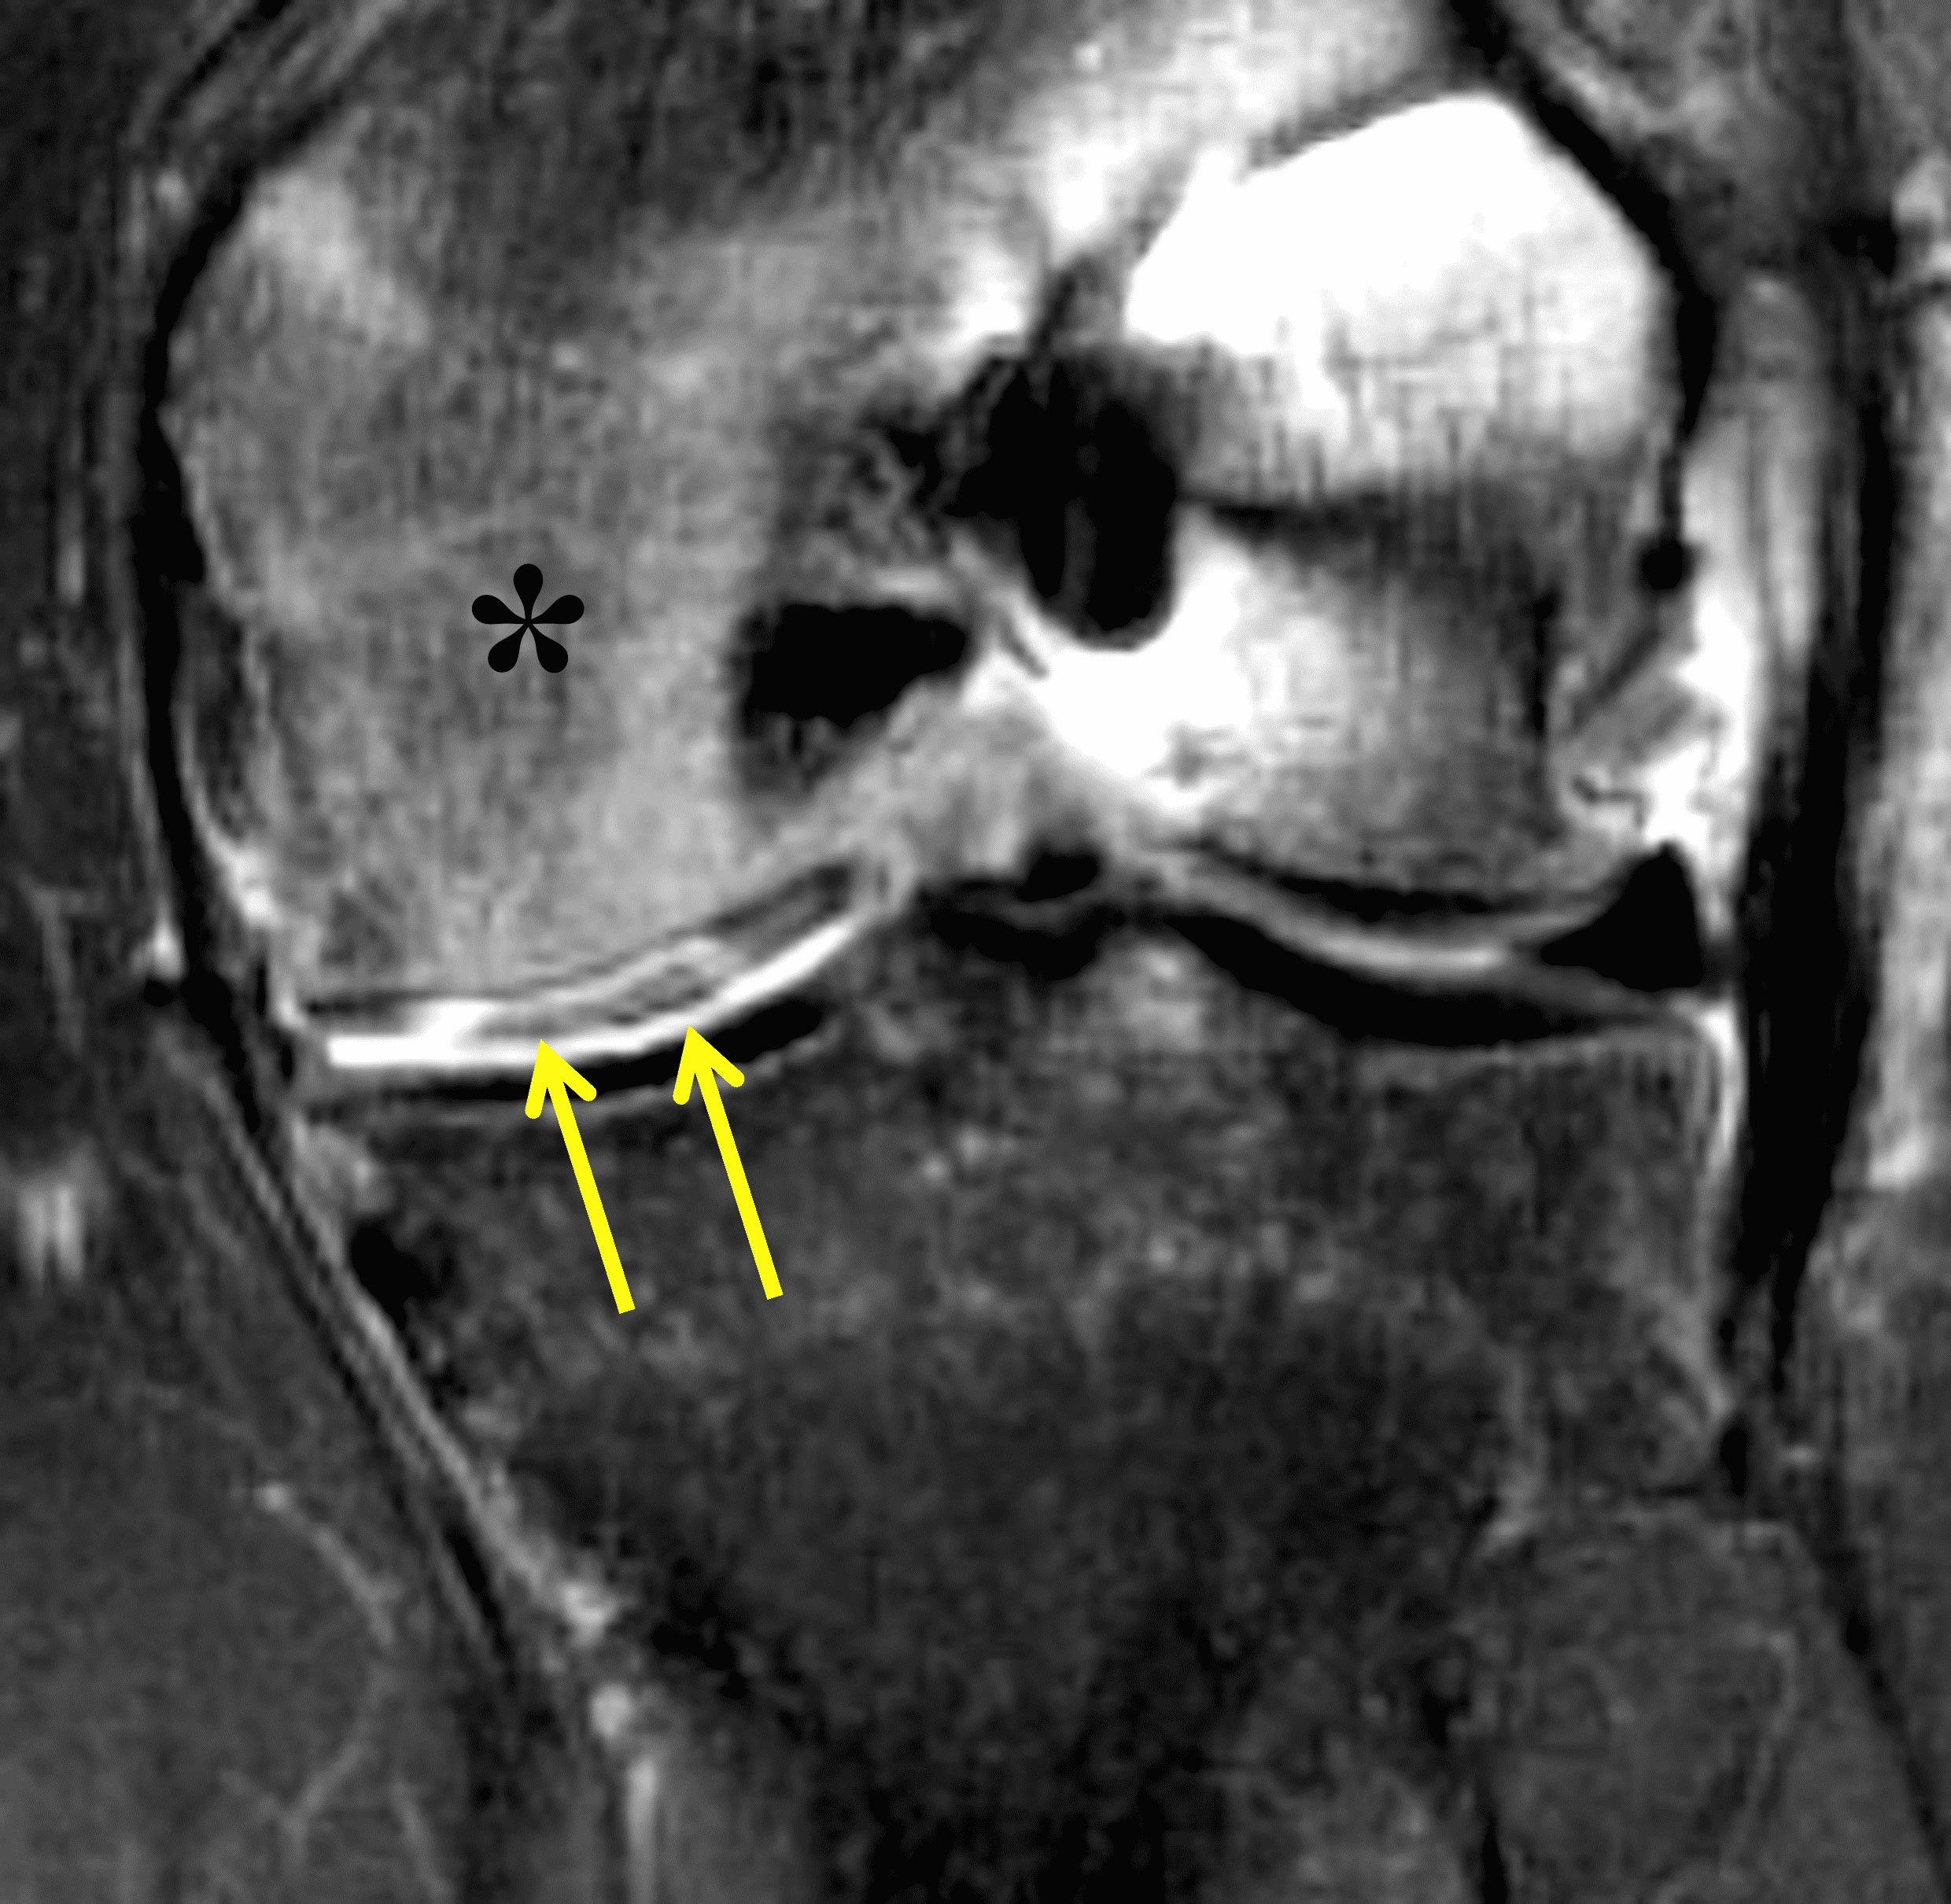

A 32-year-old man suffered a traumatic chondral injury to the medial femoral condyle that was treated with an osteochondral allograft 20 months previously. Representative images from a current knee MRI include (1A) coronal fat-suppressed fluid-sensitive and sagittal (1B) T1-weighted, (1C) proton density-weighted, and (1D) T2-weighted sequences. Are the post-operative MRI findings normal and expected, or abnormal and pathologic? Based on these images, would you characterize the procedure as a success or failure?

Figure 2: (2A) On the coronal image, the margins of the osteochondral graft are faintly visible (arrowheads). Both the graft and underlying bone show mild marrow edema, an expected finding. (2B) The T1-weighted image shows continuity of the marrow in the graft (asterisks) with the underlying bone, indicating osseous integration. A bioabsorbable pin (arrow) used for graft fixation is partly visible. (2C) The proton density-weighted image shows a low signal intensity seam (black arrow) between the native cartilage and transplant, as well as a defect in the subchondral bone plate of the graft (red arrow) where the pin was drilled, both normal findings. (2D) The T2-weighted image shows a smooth, congruent articular surface (arrows), restoring the normal anatomy, and a tiny subchondral cyst. No findings are present to suggest graft failure. The patient’s current symptoms were attributed to pathology elsewhere in the joint (not shown).

Successful osteochondral allograft procedure.

The postoperative imaging appearance of osteochondral allografts is similar to autografts (Figure 2).33 The subchondral bone plate of the donor and recipient sites do not have to match, but the articular surface should be congruent. Grafts that fail to incorporate by one year have a poor prognosis. Persistent marrow edema (beyond 12 months), a thick graft interface containing cysts or fluid, and subsidence of the graft are associated with poor osseous healing and worse outcomes. Extensive host marrow edema and severe synovitis may be a clue to immunologic rejection of the graft (Figure 18).21, 34